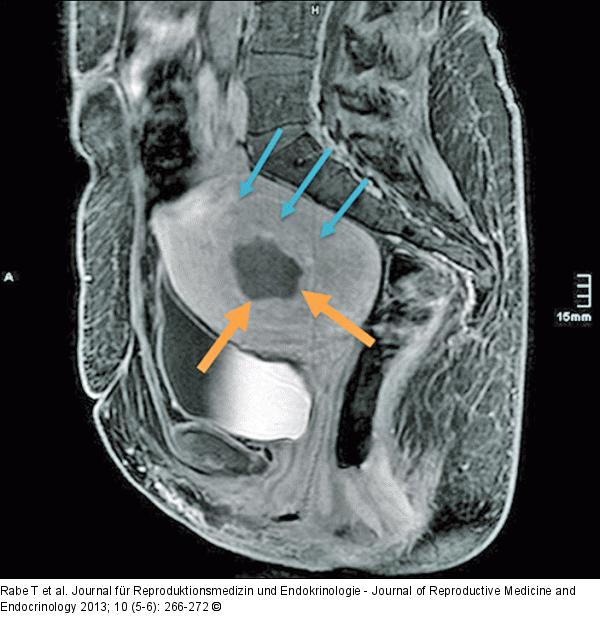

Abbildung 3d: HIFU-Behandlung Sagittale Kontrastmittel-MRT (T1-gewichtet) 4 Wochen nach HIFU-Behandlung mit Nachweis des zentralen, hypointens zur Darstellung kommenden Perfusionsdefektes des Myoms (orangene Pfeile). Differenzierung der Kapsel des submukös-intramuralen Myoms vom normalen Myometrium durch eine feine Trennschicht (blaue Pfeile). |

Abbildung 3d: HIFU-Behandlung

Sagittale Kontrastmittel-MRT (T1-gewichtet) 4 Wochen nach HIFU-Behandlung mit Nachweis des zentralen, hypointens zur Darstellung kommenden Perfusionsdefektes des Myoms (orangene Pfeile). Differenzierung der Kapsel des submukös-intramuralen Myoms vom normalen Myometrium durch eine feine Trennschicht (blaue Pfeile). |